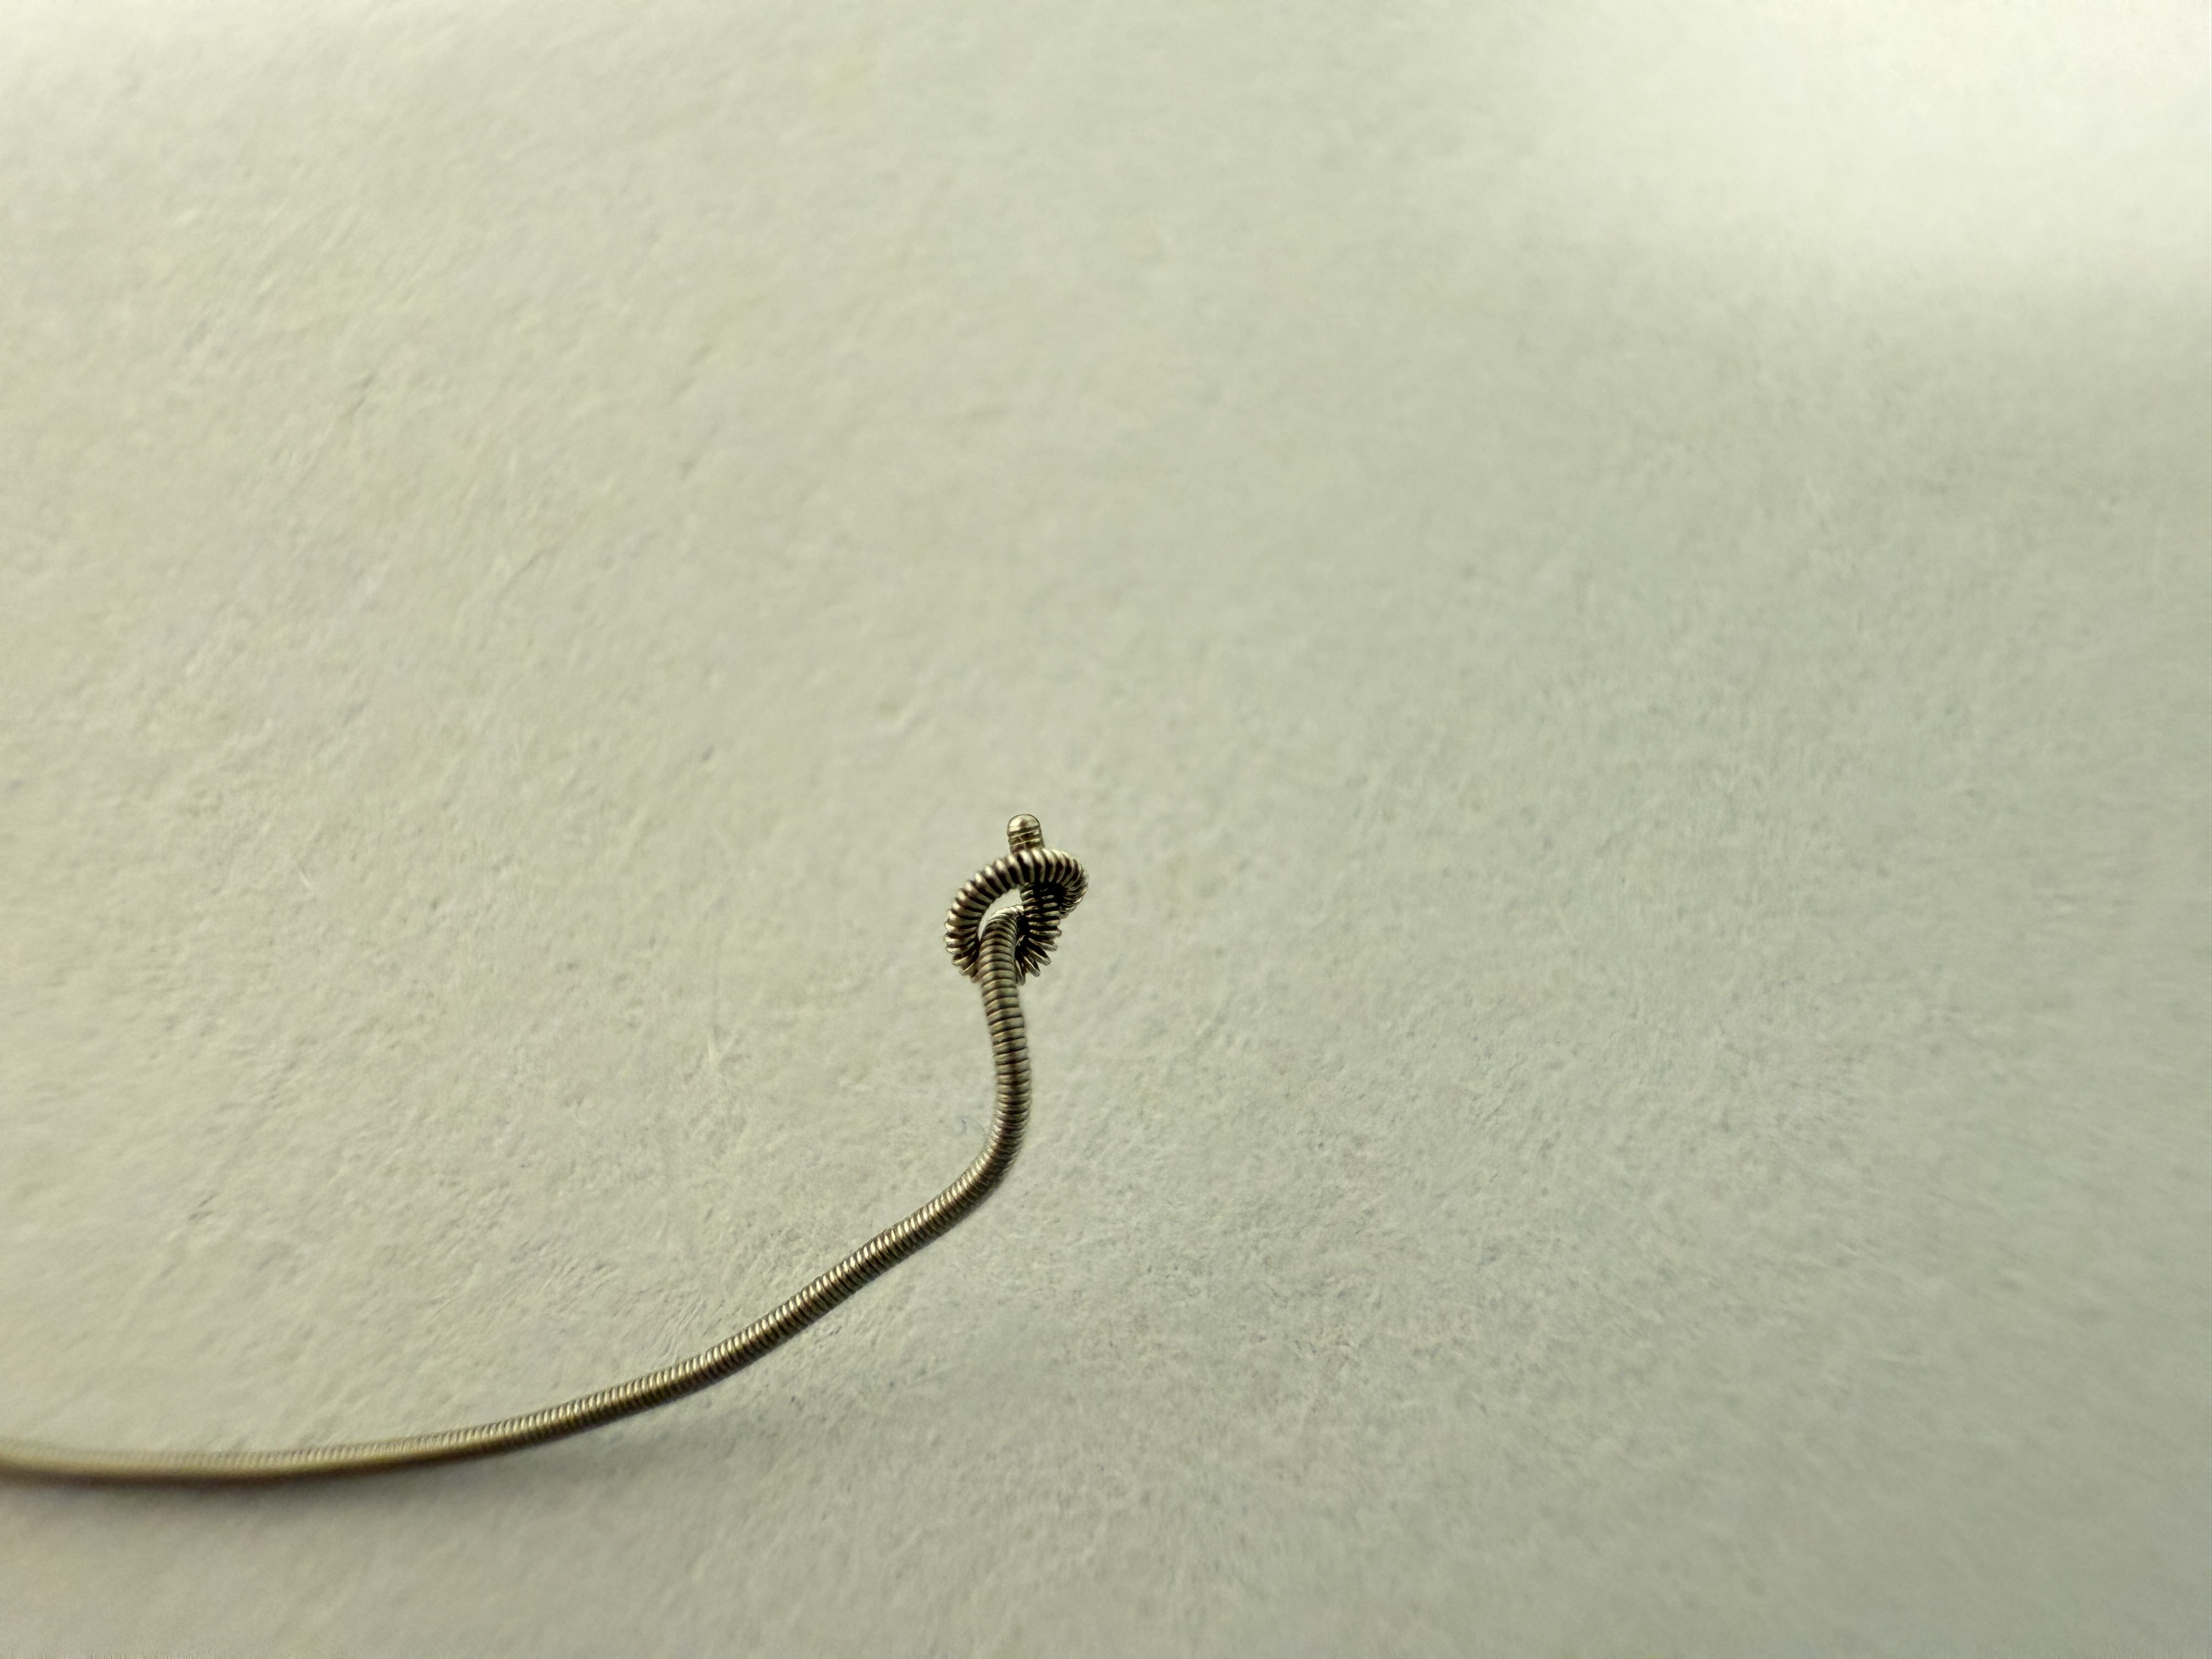

On removal of the knuckled runthrough NS, it was stucked in ventricular branch. Cine confirmed coronary guidewire knot was formed.

Finally trapped knotted guidewire was removed with Turnpike.

Guidewire knot entrapment is a rare complication and is better to be avoided.

Bailout solution includes traction with microcatheter and guide extension support.

Other solutions include parallel wire for balloon dilatation of the entrapment site, with or without a second guiding catheter.

Forcefully pulling the wire may result in retained fractured guidewire.

In our case, the entrapped guidewire knot was retrieved successfully with gentle traction with microcatheter support for en-bloc removal.

In our case, the entrapped guidewire knot was retrieved successfully with gentle traction with microcatheter support for en-bloc removal.